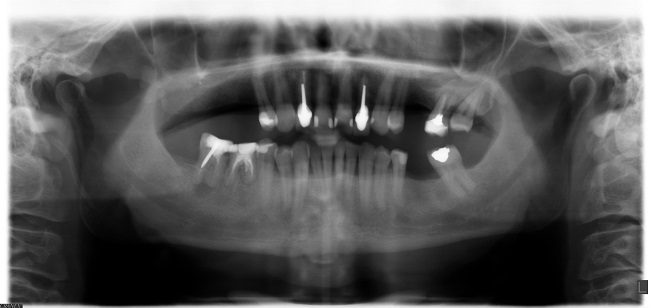

Scanner 3D ou CT scan

Pour connaitre les volumes osseux dans lesquels on peut placer vos implants dentaires, vous commencerez par passer un scanner 3D ou un CT scan (Le nom complet anglais est Cone Beam Computerized Tomography ou CBCT). Il s’agit de rayons X dont le signal de réception est traité de sorte à fournir une visualisation en 3D de votre ossature sur ordinateur. Cette technologie se différencie de la radiographie classique en 2 dimensions qui ne permet pas d’estimer les volumes des os de votre mâchoire. Toutefois, votre radiographie dentaire panoramique permet déjà à un dentiste de définir un plan de traitement et un devis pour vous poser des implants dentaires. Cela vous donnera des détails comme les techniques utilisées, le prix et les durées des deux étapes.